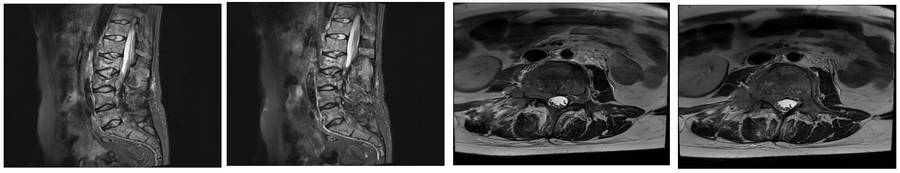

Before the surgery: MRI shows pathological fractures at two levels, as well as epidural and root compression.